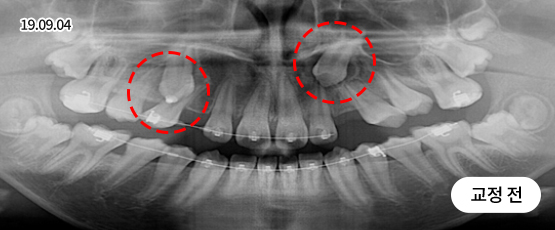

매복치 Solution

매복치는 잇몸 속에서 인접 치아에 손상을 줄 수 있어

치아 견인을 통해 제자리를 찾아주어야 정상적으로 치아가 자리 잡을 수 있습니다.

* 치근흡수, 잇몸퇴축 등 부작용이 발생할 수 있습니다.

* 본 사진은 동일 조건에서 촬영되었으며, 환자 본인의 동의를 얻어 게재되었습니다.